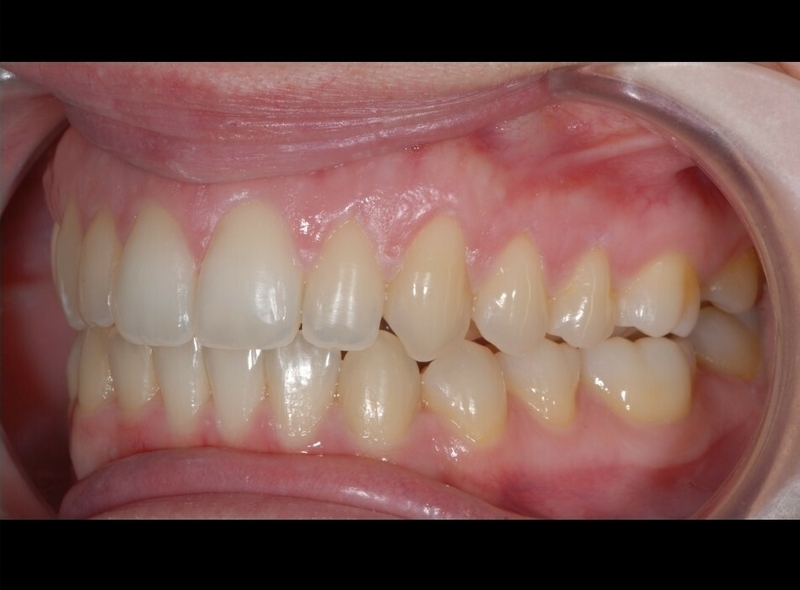

Cas clinique

Cas 1 - Orthodontie par aligneurs invisibles

Avant